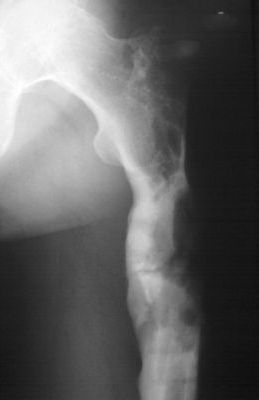

Уважаемые коллеги! Выношу на обсуждение клинический случай. Пациент 38 лет, оперирован

дважды. В настоящее время рефрактура.

Подробности из анамнеза: в 2007 году пациенту выполнена операция остеосинтез бедренной

кости по поводу многооскольчатого перелома с применением пластинки с ограниченным

контактом (имплантов с угловой стабильностью и блокируемых гвоздей на момент операции в

наличии не было - это, чтобы не обсуждать лишние вопросы).

Через 6,5 месяцев после остеосинтеза развился остеомиелит в верхней

трети диафиза бедренной кости с образованием секвестра размерами

55х30х25 мм. В 2008 году (через 8 месяцев после остеосинтеза)

выполнена вторая операция - удаление металлоконструкции и

секвестрэктомия. При удалении пластинки и ревизии ложа секвестра,

костная мозоль на сросшемся участке состоятельна. было принято

решение заполнить секвестральную полость мышечным лоскутом.

В настоящее время госпитализирован для оперативного лечения по поводу

рефрактуры на уровне верхней трети бедренной кости. Планируется остеосинтез аппаратом